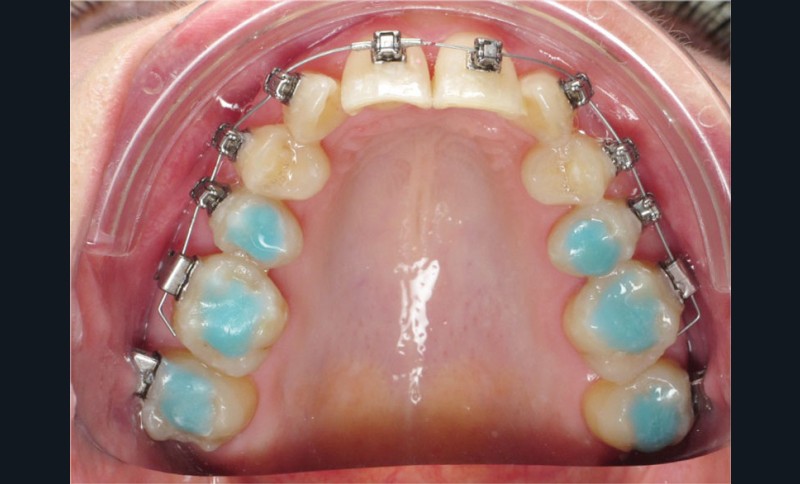

Un appareillage Damon métal a été mis en place, réalisé à partir d’un set up numérique Insignia pour obtenir un contrôle précis des torques et de la forme d’arcade et réduire le temps de finition grâce à un collage indirect très précis.

De larges surélévations postérieures étalées ont été mises en place et la patiente a porté des élastiques précoces suivant les principes de la technique Damon. Les 14 et 24 rempliront le rôle des 13 et 23.